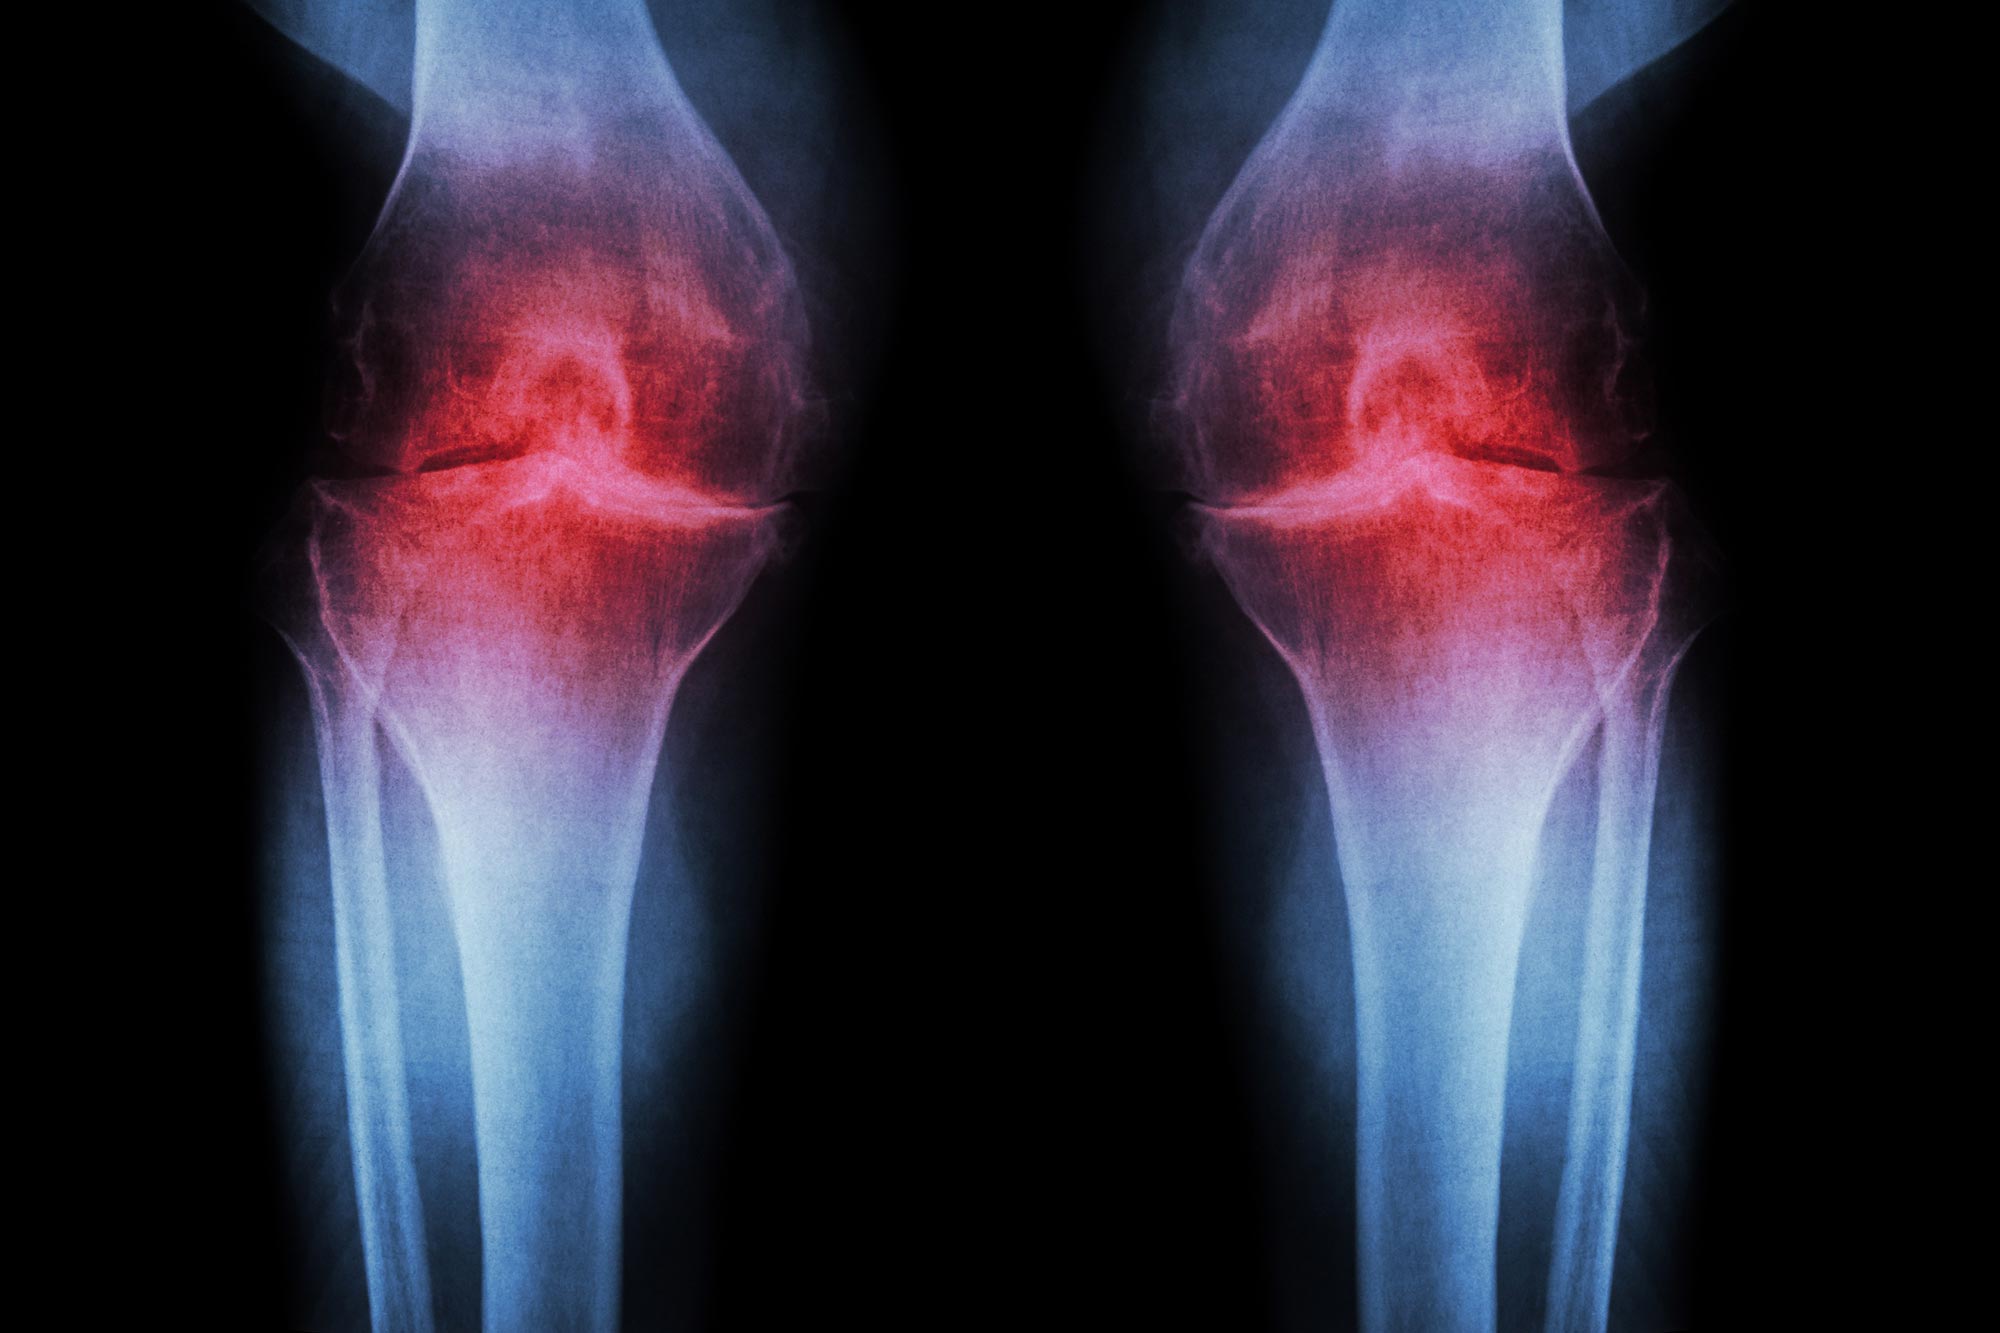

Arthritic diseases include rheumatoid arthritis and psoriatic arthritis, which are autoimmune diseases; septic arthritis, caused by joint infection; and the more common osteoarthritis, or degenerative joint disease. Arthritis can be caused from strains and injuries caused by repetitive motion, sports, overexertion, and falls. Unlike the autoimmune diseases, osteoarthritis largely affects older people and results from the degeneration of joint cartilage. Other forms are discussed below.

The various types of arthritis can be distinguished by the pace of onset, the age and sex of the patient, the amount of (and which) joints affected, additional symptoms such as psoriasis, iridocyclitis, Raynaud's phenomenon, and rheumatoid nodules, and other clues.Blood tests and X-rays of the affected joints are often performed to make the diagnosis. X-rays can show erosions or bone appositions.

Nearly a quarter of people over the age of 40 experience painful osteoarthritis, making it a leading cause of disability in adults. Osteoarthritis degrades joint-cushioning cartilage, and there is currently no way of reversing this damage: the only option is to manage pain with medication, and eventually, joint replacement.